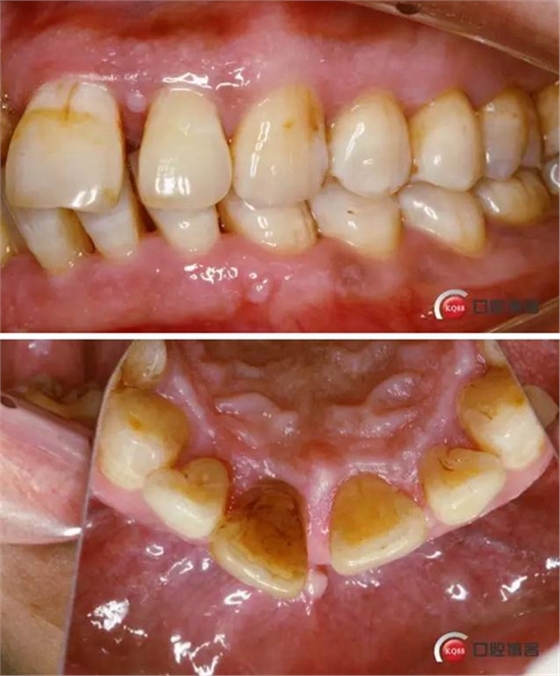

術(shù)前口內(nèi)照